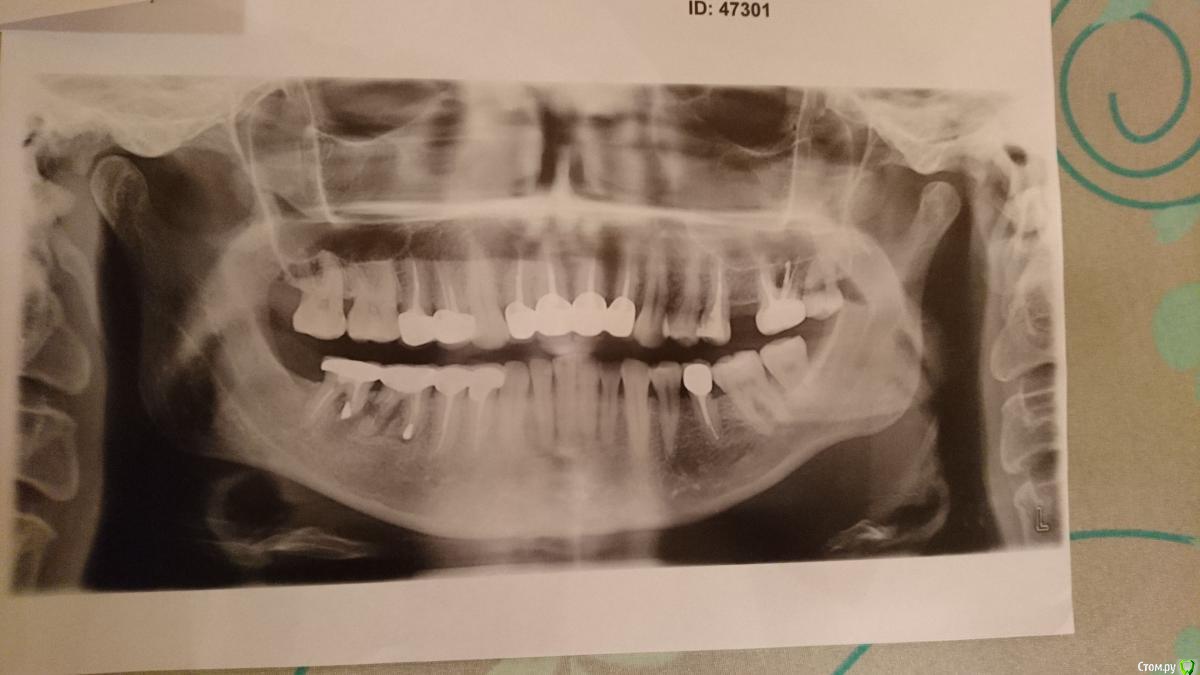

Наталья_3323 Опубликовано 1 июня, 2018 Поделиться Опубликовано 1 июня, 2018 Добрый день, уважаемые врачи! Прошу оказать помощь и посоветовать план лечения. 2016 год я установила коронки (см.снимок – выделено цветом), врач установил 4 коронки одним мостом (до сих пор не понятно почему). Через год (2017), на десне, ближней к щеке, стали образовываться гнойные образования, которые лопались и затем опять набухали, эта ситуация продолжалась около 10 месяцев. В начале 2018 года образования перестали возникать, но на десне, до сих пор есть образования, но они не гноятся и не набухают. Сделала снимок, врач сообщил, что под коронкой разрушаются корни и видно, что там образовались пустоты, которые носят характер распространяющихся со временем. Решение – удалять зубы под коронками и ставить имплантаты. Установка имплантатов не возможна без удаления корней под коронками. Уточните, пожалуйста: 1. Есть ли альтернативное решение по моей ситуации?2. Можно ли сохранить коронки на соседних зубах, где нет разрушения корней и какова вероятность, что через некоторое время корни под этими зубами тоже не начнут разрушаться и не придется устанавливать и на эти зубы имплантаты? Заранее благодарю! Ссылка на комментарий

kramer Опубликовано 1 июня, 2018 Поделиться Опубликовано 1 июня, 2018 6, 7 удалять. На 4 и 5 я бы переделал коронки, сделав их одиночными. 1 Ссылка на комментарий

red_butler Опубликовано 1 июня, 2018 Поделиться Опубликовано 1 июня, 2018 альтернатива моей ситуации. обязательно ставить импланты на все 4 зуба, можно ли залечить корни и пр... конструкцию распилить - это временное решение? т.е. на 4 и 5 в любом случае нужны будут новые коронки?6 и 7 однозначно удалять. 5 и 4 оценивать очно и скорее всего после снятия коронок. Если 4 и 5 останутся, то потребуется их новое протезирование. 1 Ссылка на комментарий